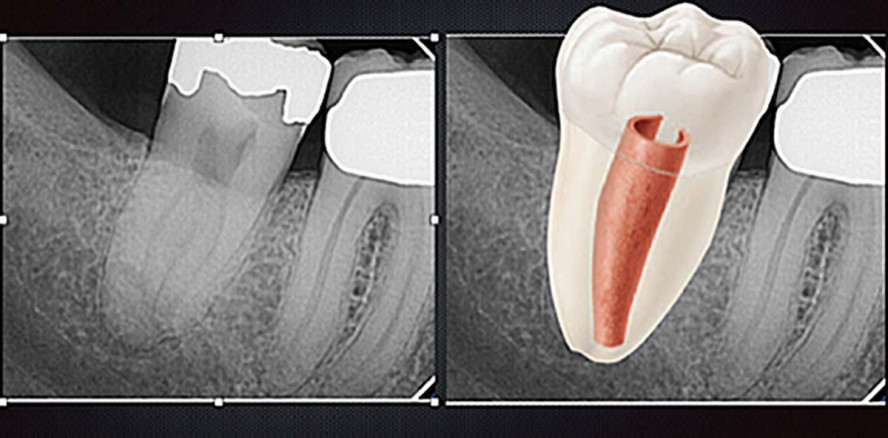

Die meisten Zähne mit einer c -förmigen Kanalkonfiguration sind mit einer Einzelzahnaufnahme zu identifizieren (Abb. 3). Die Wurzeln sind fusioniert und zeigen eine konische Erscheinung. Die Wurzelkanäle vereinigen sich kurz vor dem Apex. Ist man trotzdem nicht sicher, ob es sich um eine c -förmige Wurzelkonfiguration handelt, dann ist die Erstellung einer DVT-Aufnahme sinnvoll. Mit der horizontalen Darstellung lässt sich die Kanalkonfiguration sehr gut bestimmen. Die Wanddicke und die Dimension der Pulpa lassen sich ebenfalls gut einschätzen und sind somit für die Behandlungsplanung sehr hilfreich. Bei der klinischen Untersuchung müssen alle Tests (Sensibilität, Perkussion, Palpation etc.) durchgeführt werden, um den Zustand der Pulpa und des periradikulären Bereiches bestimmen zu können. Ebenso wichtig ist die Messung des parodontalen Zustandes. Wegen der schwierigen Behandlung von Zähnen mit einer c -förmigen Wurzelkanalkonfiguration sollte bei einer ausgeprägten parodontalen Erkrankung sehr genau überlegt werden, ob eine endodontische Behandlung des Zahnes noch sinnvoll ist.

Zähne mit einer c -förmigen Kanalkonfiguration sind in sehr vielen morphologischen Variationen zu finden. Die am häufigsten verwendete Klassifikation von Melton et al. ist in der Abbildung 1 aufgeführt. Eine „klassische“ c -förmige Kanalkonfiguration hat einen durchgängigen Isthmus, der die Form eines „c“ hat, wobei die Rundung meist bukkal liegt. Dieses Muster folgt vollständig oder teilweise bis zum Apex. Eine andere häufige Konfiguration beinhaltet ein Dentinband an einem Ende des Isthmus. Die Form ähnelt einem Semikolon. Eine weitere Konfiguration zeigt einen mesialen und/oder distalen Kanaleingang wie in einem üblichen Molaren und einem schmalen Isthmus (Abb. 2). Eine weniger häufige Konfiguration ist ein symmetrisch angelegter mesialer und distaler Kanaleingang im Oberkiefermolar. Ein Isthmus ist nicht vorhanden, aber es zeigt sich eine aus mehreren Wurzeln verschmolzene Wurzel.